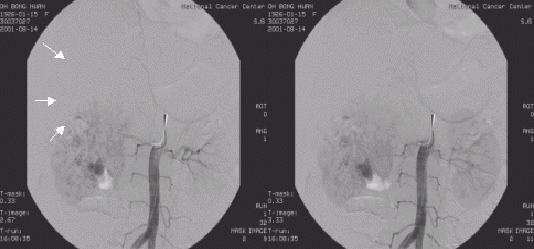

○ 신동맥조영술

주로 신장이 하나 뿐인 환자(반대편 신장의 기능부전이 있는 경우 포함)에서 발생한 신세포암이나 양측신장에 발생한 신세포암의 경우 신보존술을 시행하기 전에 혈관분포를 파악하기 위해서, 혹은 수술이 불가능하여 신동맥색전술을 시술할 때 시행합니다.

그림 5. 우측 신장암환자의 신동맥조영술사진